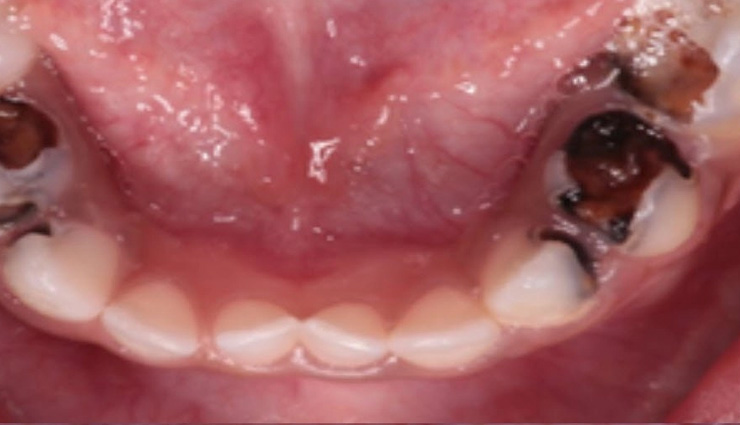

# Missing Teeth

Tooth loss in seniors can result from cavities, root decay, fractures, and other issues. Missing teeth or gaps can hinder proper chewing, leading to nutritional deficiencies and digestive problems.